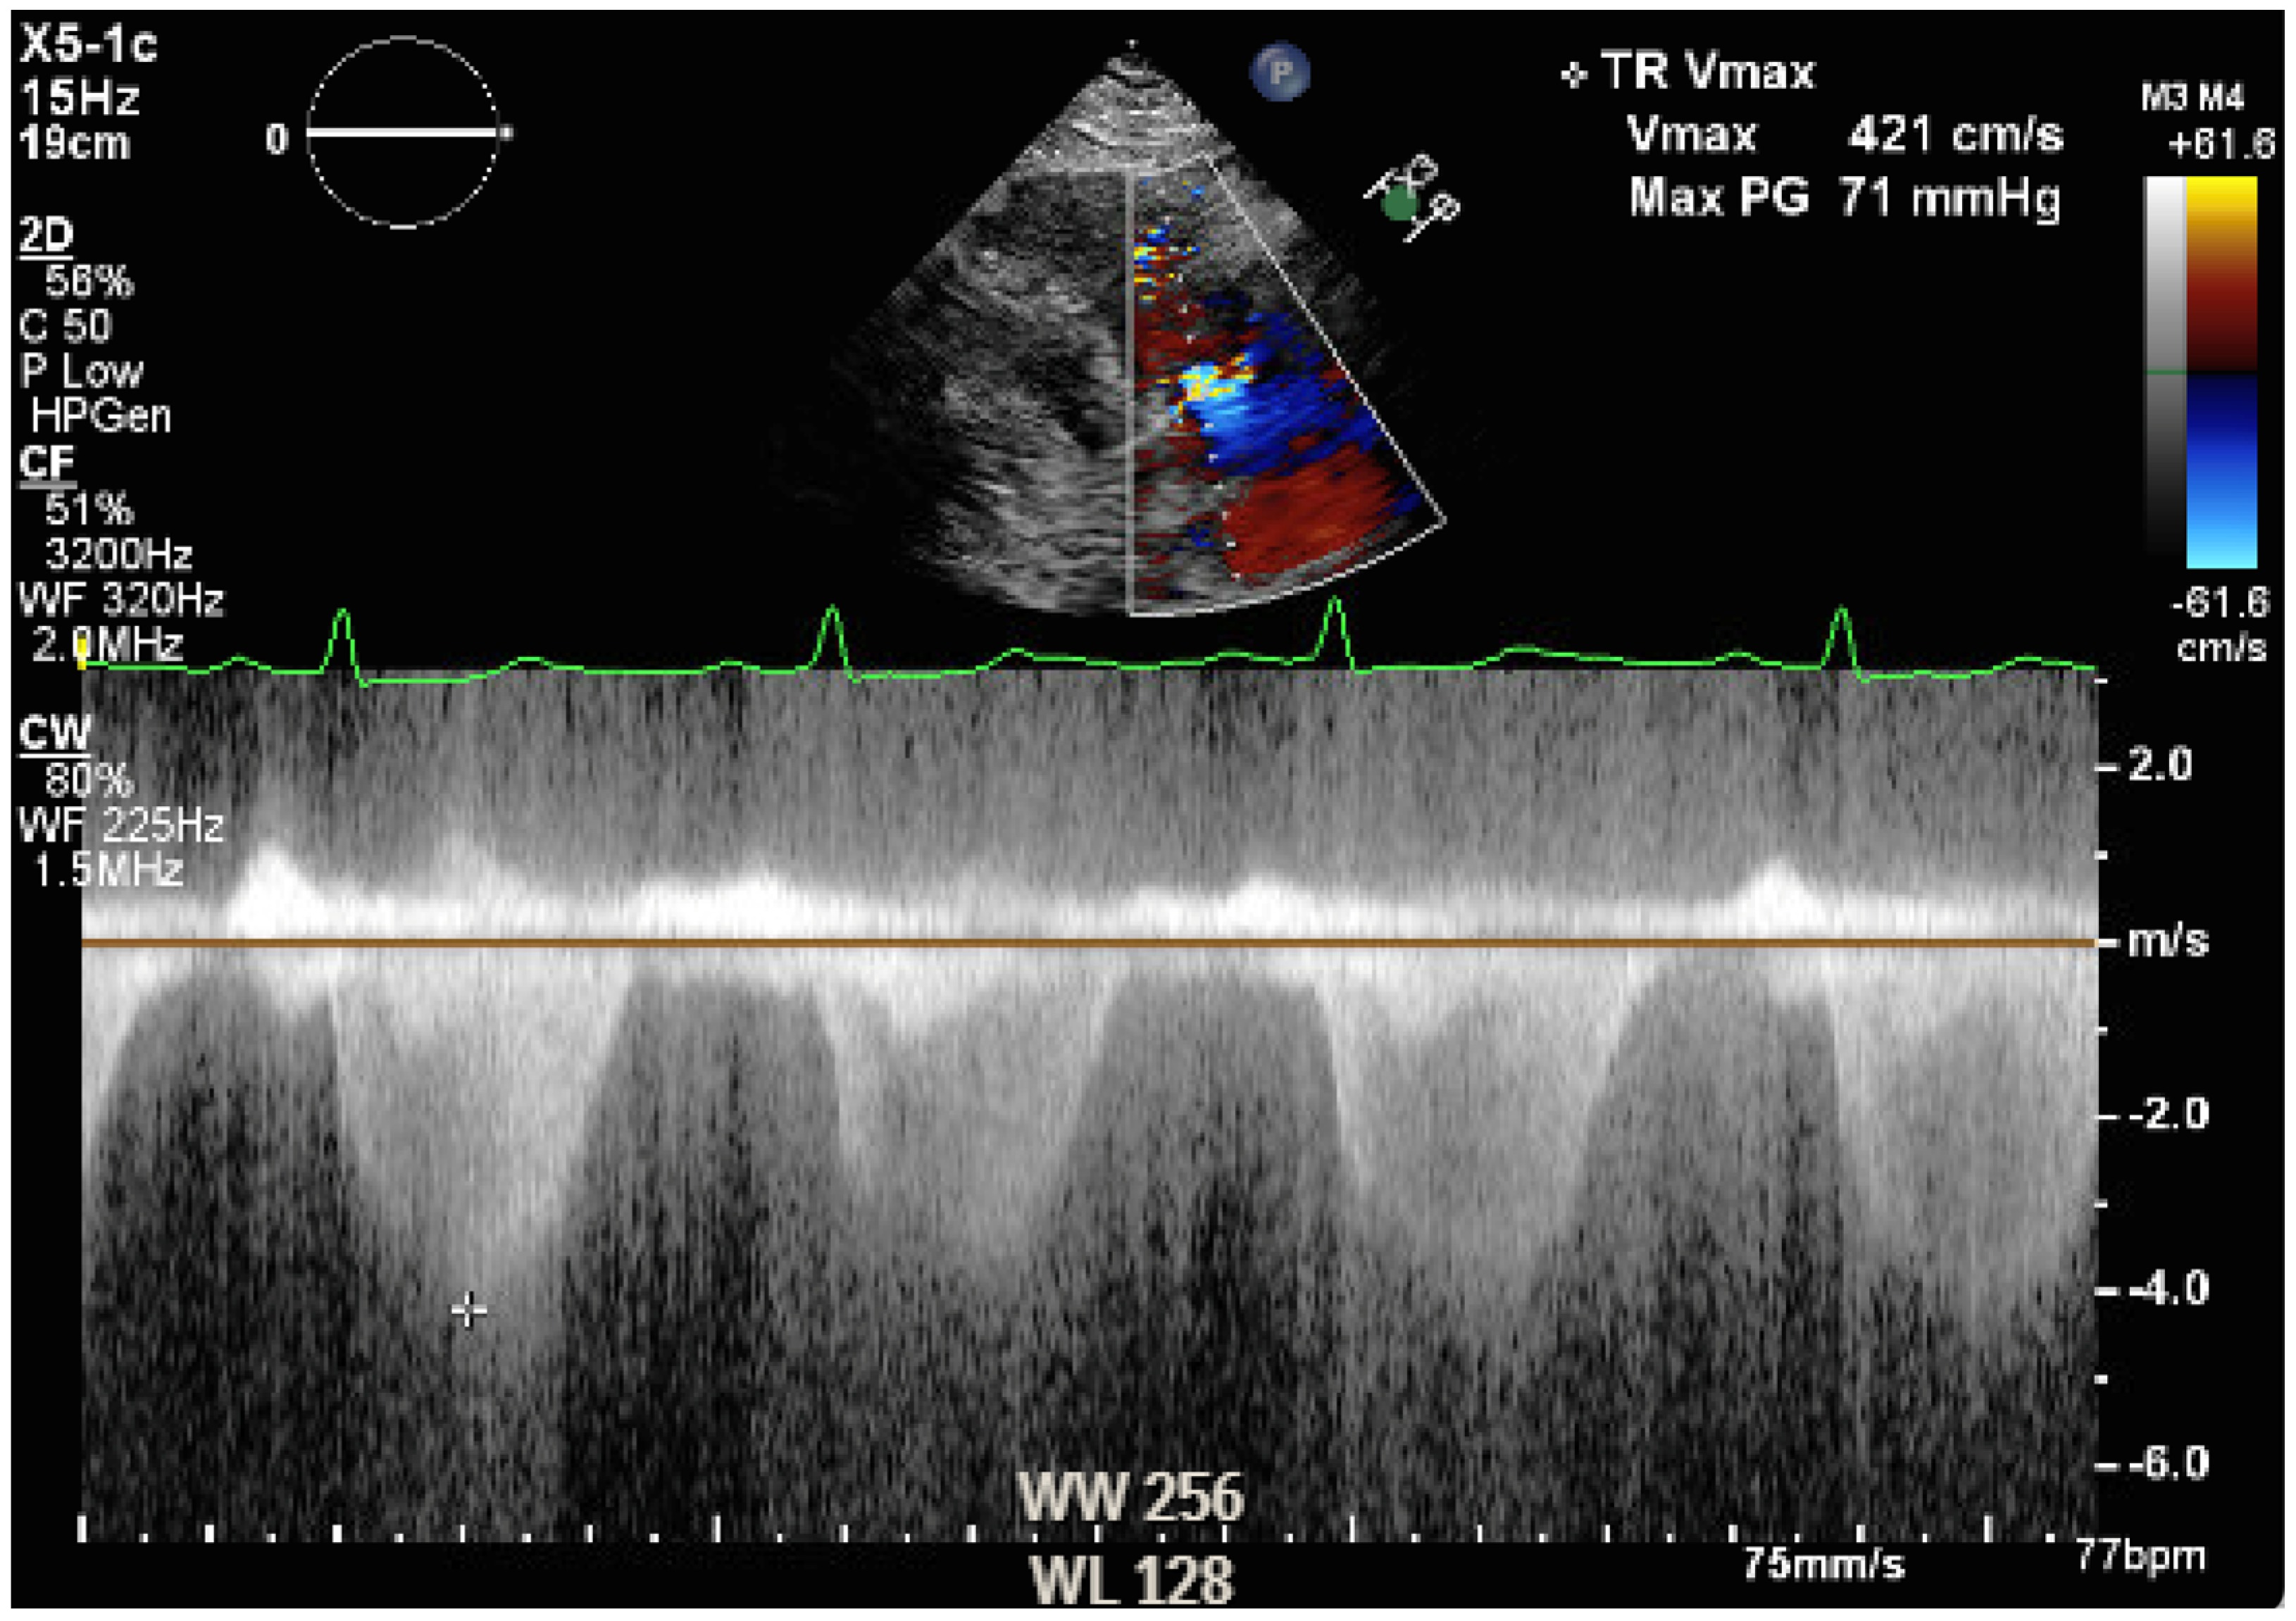

The intraoperative course was not characterized by major complications. MELD 3.0 and MELD-Na were 24 and 23, respectively, on the day of surgery. The surgical procedure consisted of the piggyback technique and portal thrombectomy. Cold ischemic time was 5 h and 46 min, and warm ischemic time was 19 min. Intraoperatively, the patient’s hemodynamic parameters were stable and supported with phenylephrine and norepinephrine during the reperfusion and neo-hepatic phase, while hypertension control with labetalol was required at the emergence. Transesophageal echocardiography showed findings comparable to rest transthoracic echocardiography (Video S2a,b). Hemodynamic monitoring was performed with transesophageal echocardiography, monitoring central venous pressure (CVP), urine output, and trending lactic acid as marker of perfusion. No Swan-Ganz catheter was placed intraoperatively. The patient received a total of 1.8 L of crystalloids, 2 L of albumin, 6 units of packed red blood cells, 2 units of fresh frozen plasma, and 2 L of processed blood from cell saver. Blood loss was estimated to be of 3 L, and urine output was 1 L after 20 mg of furosemide. The patient was extubated in the operating room and transferred to the surgical ICU. During the postoperative period, volume status was monitored with CVP, non-invasive blood pressure, and trend of lactic acid. He did not require any diuretics while urine output was adequate, and he was started on nifedipine for hypertension, he required insulin to control hyperglycemia, and he complained of dyspnea on exertion, which was primarily attributed to acute postoperative anemia. The immunosuppressant medications consisted of induction with steroids, which were tapered until interruption, and maintenance with tacrolimus and mycophenolate mofetil. The patient was transferred to the floor on postoperative day (POD) 2 and discharged home on POD 6. However, on POD 8, he was readmitted for self-limited episodes of confusion, dyspnea, and leg swelling. An electrocardiogram showed T wave inversion in the anterior leads, Troponin I was 0.13 ng/mL (versus 0.04 on POD 5, upper limit of normal 0.08 ng/mL), and an arterial blood gas analysis showed hypoxemia and hypocapnia on room air. An echocardiogram revealed flattened interventricular septum as per right ventricle overload, severe dilation of right ventricle along with severely reduced systolic function, normal left and right atrial size, and an estimated pulmonary artery systolic pressure (PASP) of 70–75 mmHg (Video S3, Figure 3).

Figure 3.

Pulmonary artery systolic pressure estimation.